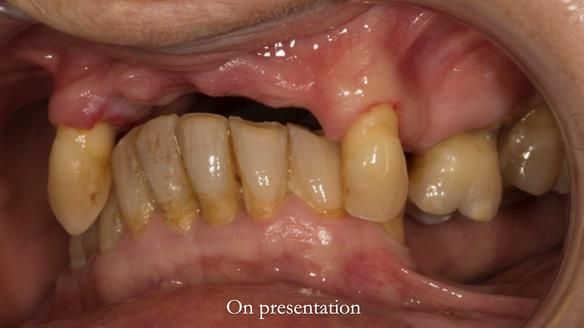

In this edition, I present the removable partial denture treatment for Jean, an 80-year-old woman with a sore mouth caused by a soft tissue-supported 'gum stripper' acrylic denture and a clenching habit. Below, I outline the step-by-step process of her treatment. It wasn't straightforward; I had to remake the denture after it fractured to achieve a satisfactory result. Each patient is unique, and sometimes a new RPD serves as a prototype. Occasionally, I need to make adjustments, learn from any mistakes, and refine the design to get it right.

The treatment has been a success over the past 4 years.